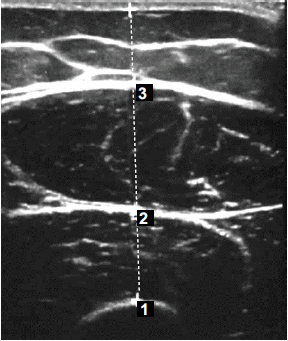

The main outcome for comparing groups was MLT. Participants visited the radiology department 1-3 days before surgery (preoperative measurement), 14 days, and 4 weeks post-operatively. Transverse B-mode images were acquired using an ultrasound machine (Logiq E9; Medical Systems, Milwaukee, WI, USA) and a 10-MHz linear transducer. To maintain standardisation of MLT measurement, participants were present at the same time of the day during every ultrasound assessment visit. Participants were in a semi-supine position, hips in neutral position, and knees at full extension, while pillows were situated at the ankles to avoid any accessory movements during assessment. Using a tape measure, the area between the anterosuperior iliac spine and the lateral epicondyle was measured, and the midpoint was marked with a permanent marker to establish a standardised MLT assessment area.

A.A. conducted ultrasonic imaging of the RF and VI, with each muscle measured three times during the assessment session. At the same session, MLT was then obtained using an integrated ultrasound arrow (Fig. 2), to the nearest millimeter, and the median value was derived for the data analysis. The MLT of both RF and VI was determined by the distance between the two heads of the arrow.

Ultrasound image of the anterior thigh 4 weeks following anterior cruciate ligament reconstruction.